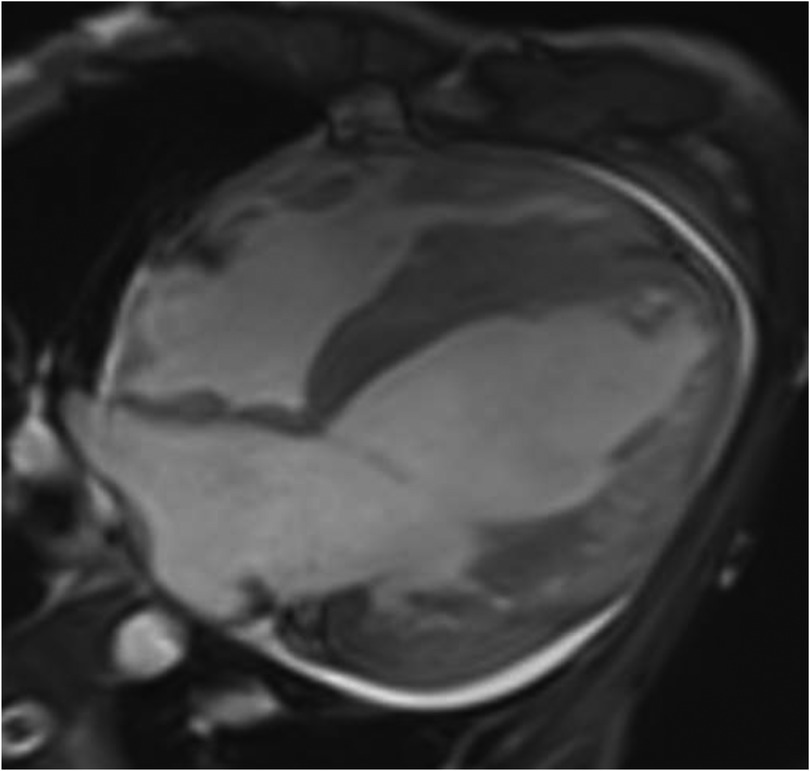

Cardiac magnetic resonance (CMR) plain scan + enhanced scan showed the following: (1) left ventricular dilatation with decreased systolic function (EF 19%) thinning of the left ventricular free wall and apex, weakened movement, and increased and disordered trabeculae, considering LVNC; late enhancement of the left ventricular anterior wall, lateral wall, inferior wall, and apex, suggesting myocardial fibrosis or scar; (2) thickening of the left ventricular septum and right ventricular myocardium, with a high possibility of HCM; and (3) pericardial effusion (Figure 2).

Figure 2

CMR four-chamber heart long axis: left ventricular dilatation, thinning of left ventricular free wall and apex, with increased and disordered trabeculae, presenting a spongy appearance.